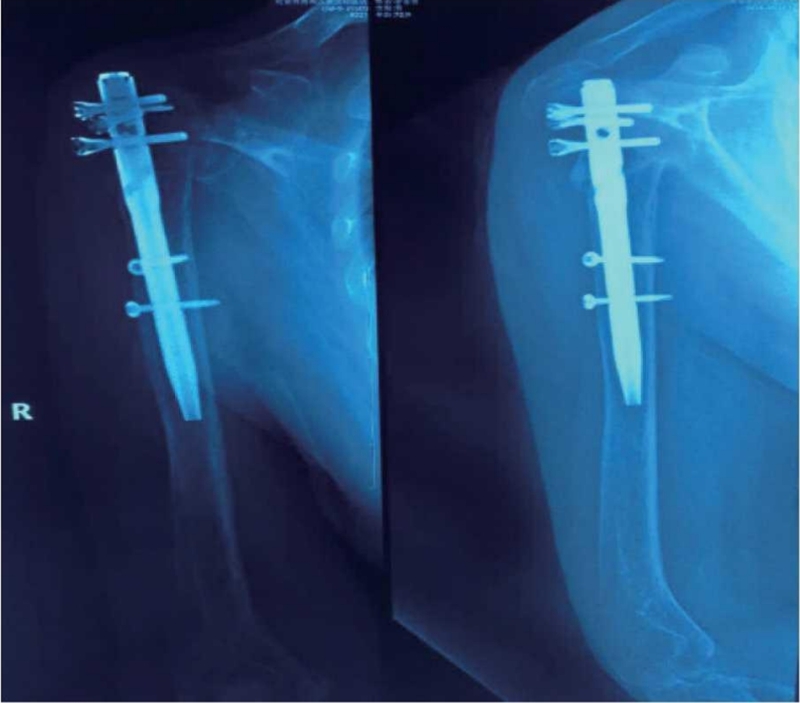

肱骨近端骨折内固定术后整体并发症发生率为30%。其中,常见的并发症主要有螺钉切出/穿透关节面、肱骨头内翻畸形、肱骨头缺血坏死、髓内钉移位、骨折不愈合、内固定断裂等(图1~3)。

图3 肱骨近端骨折逝内钉内固定术后内固定移位